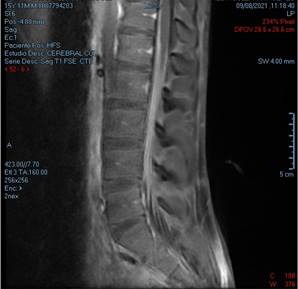

La resonancia magnética de columna contrastada evidenció “engrosamiento e hipercaptación del medio de contraste en las raíces nerviosas, que conforman la cauda equina, comprometiendo desde T12 hasta la región sacra” Figura 1.

Figura 1 Columna toracolumbar en T1 que evidencia engrosamiento e hipercaptación del medio de contraste en las raíces nerviosas, que conforman la cauda equina, comprometiendo desde T12 hasta la región sacra.